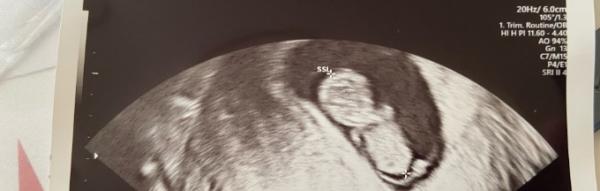

Heute wegen Blutungen in der Notaufnahme gewesen ( ist aber alles super ) Ist gewachsen hüpft rum, Herzchen schlägt kräftig Das Bild was hier angeheftet is vaginal. Unten in den Kommentaren mach ich Bauch noch

Laut Periode 10+2 laut Baby 9+5